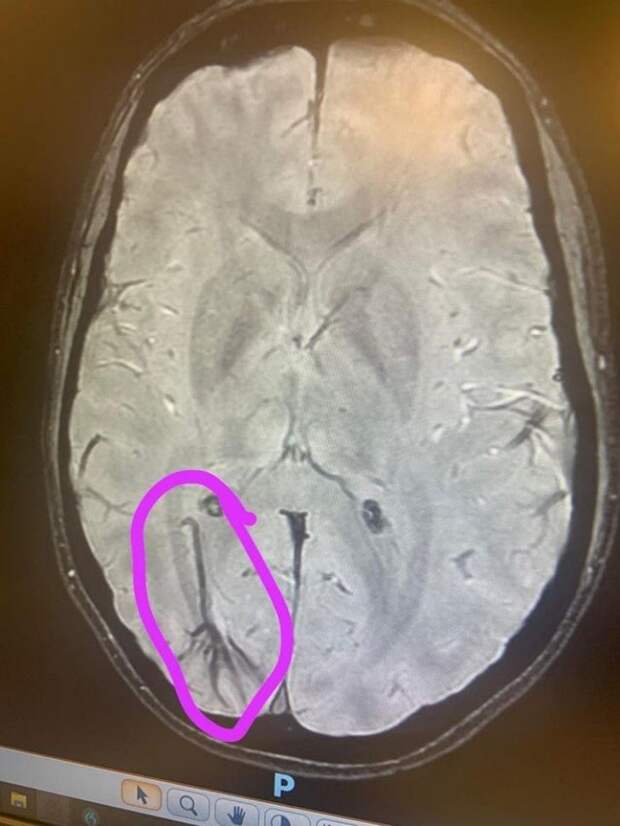

«На сканировании врач обнаружил вену пуповины у меня в мозгу. Она должна была исчезнуть до рождения. Теперь у меня есть оправдание, когда я веду себя по-детски»